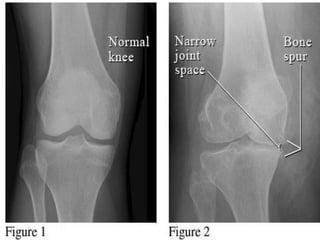

MORPHOLOGY

• Gross picture:

1) Granular, irregular articular cartilage as it

becomes soft due to degradation.

2) Eventually full thickness portions of cartilage

are sloughed exposing subchondral bones

which now become new articular surface.

3) Friction smoothens bony surfaces giving it

appearance of polished ivory (bone

eburnation).

4) Sclerosis of underlying bone.

• Mushroom shaped osteophytes (bony

outgrowths) develop at margins of

articular cartilage & are capped by

cartilage that gradually ossify.